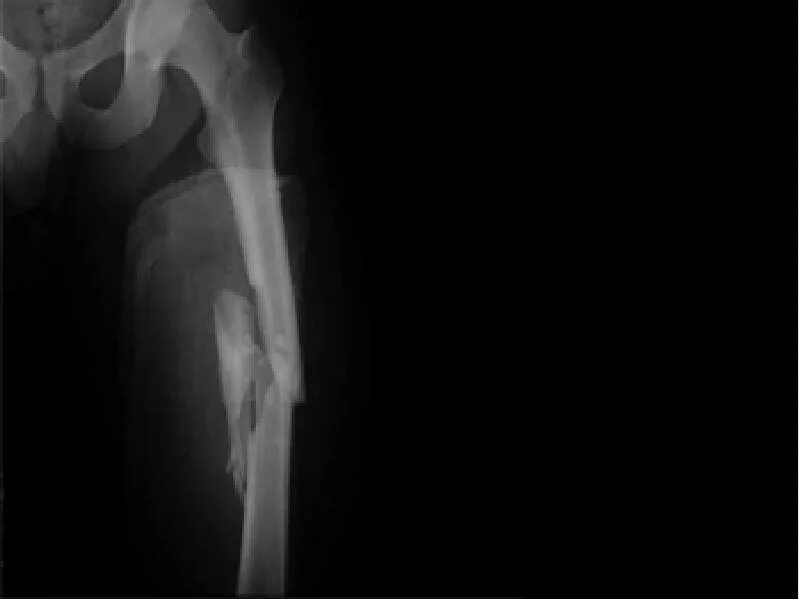

Перелом 1 3 бедра